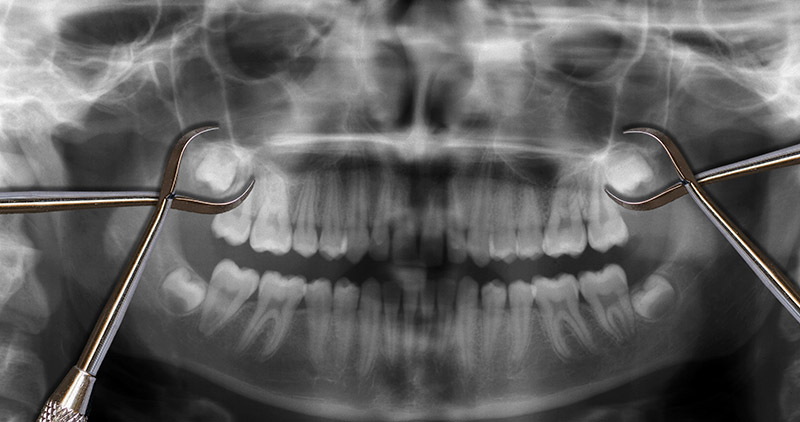

Most wisdom teeth start making their appearance between ages 15–25. Regular checkups — especially digital X-rays — help us track how these molars are forming, the direction they’re growing, and whether they’ll cause trouble.